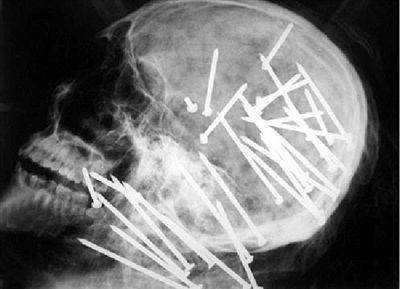

• 19.他被射入了三十枚钉子,然后被人用绳子和电线捆绑起来,再用一块地毯卷扎起来扔进冰河里,我们不妨叫他拉斯布丁,还有王法么?